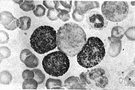

| Noun | 1. |  cancer of the blood - malignant neoplasm of blood-forming tissues; characterized by abnormal proliferation of leukocytes; one of the four major types of cancer cancer of the blood - malignant neoplasm of blood-forming tissues; characterized by abnormal proliferation of leukocytes; one of the four major types of cancercancer, malignant neoplastic disease - any malignant growth or tumor caused by abnormal and uncontrolled cell division; it may spread to other parts of the body through the lymphatic system or the blood stream acute leukemia - rapidly progressing leukemia chronic leukemia - slowly progressing leukemia lymphocytic leukemia - leukemia characterized by enlargement of lymphoid tissues and lymphocytic cells in the circulating blood histiocytic leukaemia, histiocytic leukemia, monoblastic leukaemia, monoblastic leukemia, monocytic leukaemia, monocytic leukemia - leukemia characterized by the proliferation of monocytes and monoblasts in the blood myeloblastic leukemia - a malignant neoplasm of blood-forming tissues; characterized by numerous myeloblasts in the blood stream granulocytic leukemia, myelocytic leukemia - a malignant neoplasm of blood-forming tissues; marked by proliferation of myelocytes and their presence in the blood |